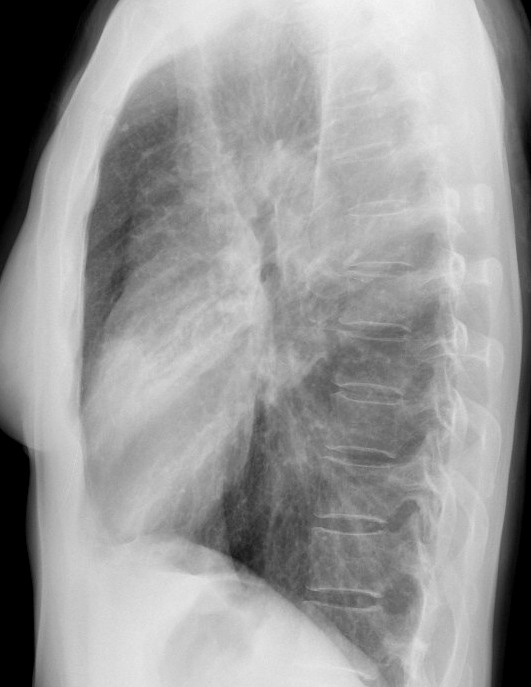

Case 2  Lingular pneum Lat